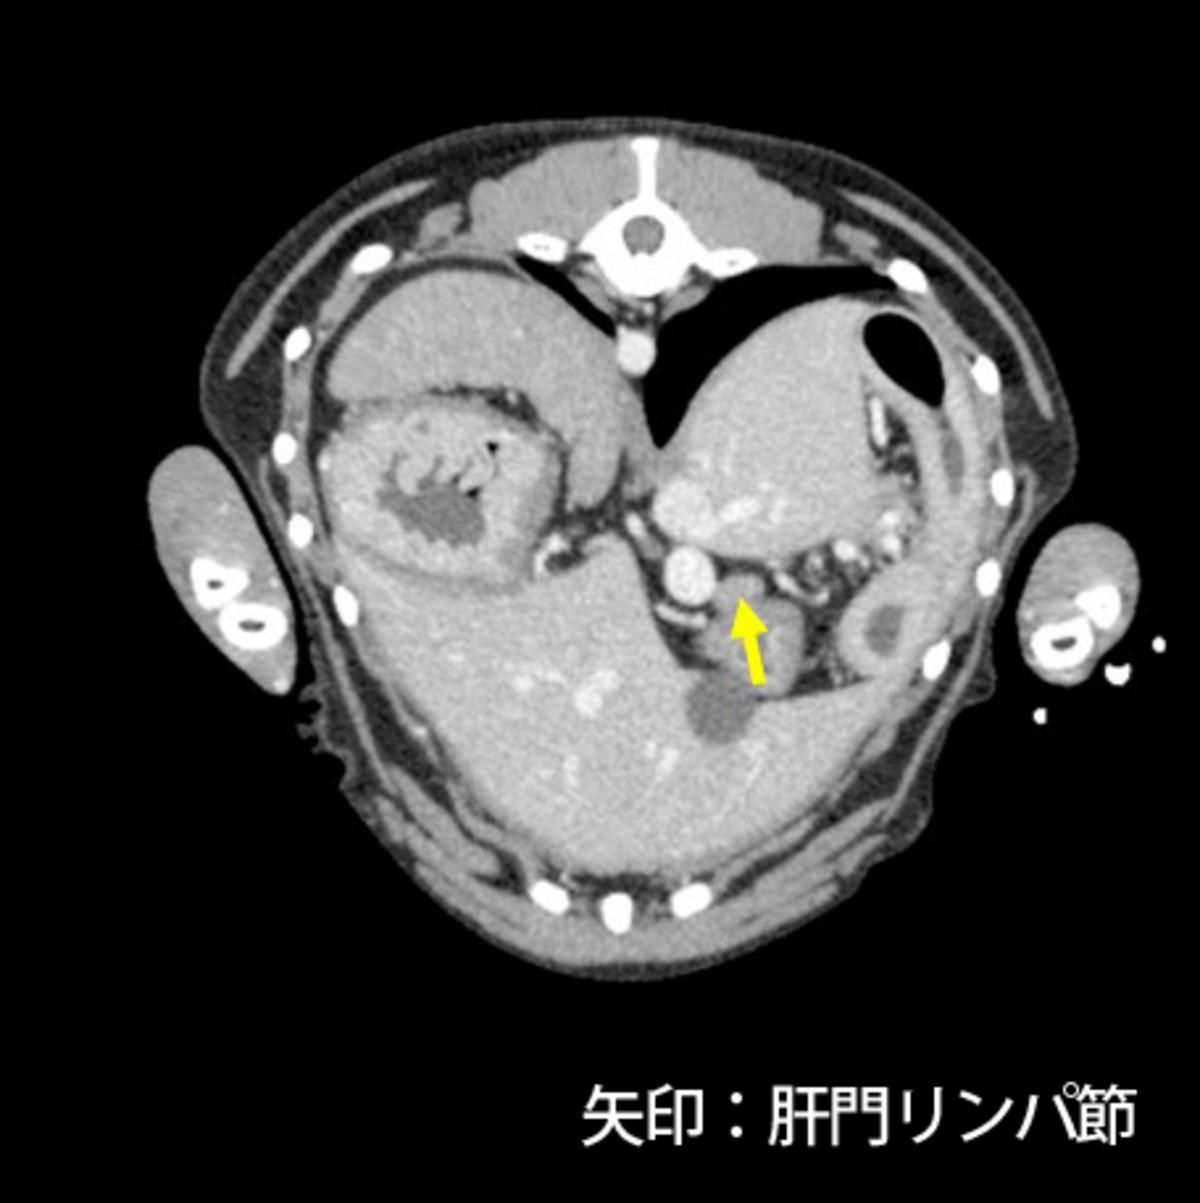

症例はバセンジー、去勢雄、11歳8ヵ月齢、10.5kgです。当院初診の一月前にふらつきを認め近医を受診し、低血糖(38mg/dL)、インスリン高値が認められたためインスリノーマと仮診断され、少量頻回の食事と糖液の投与により一般状態を維持していました。初診時の血液検査では血糖値は正常であり、CT検査にて膵臓右葉尾側に腫瘤(15×10×10mm)、肝臓外側左葉の腫瘤(5mm大×2)、肝門リンパ節腫大(12×10×6mm、15×9×7mm)が認められました(図1)。肝臓への転移が疑われるため、根治は難しい可能性が高いものの臨床症状およびQOLの改善を目的とした手術が予定されました。

図1.CT検査にて膵臓腫瘤(図1-1)、肝門リンパ節腫大(図1-2、1-3)を認めた